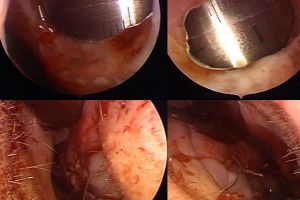

В первом случае была спонтанная перфорация размером 2 на 1,7 см у любителя "ковыряться" в носу. Пациента помимо сухости и образования корочек беспокоили носовые кровотечения. Фото 1, 2.